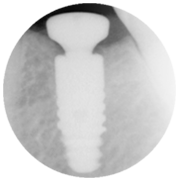

The unique friction-lock and keyed TissueCare connection creates such a close fit between the two components that subcrestal implant placement is possible. This leads to a positive bone response, enabling the desired emergence profile and transgingival healing.

In other words, Ankylos offers the versatility of a twopiece system while maintaining healthy hard and soft tissue and keeping it free from irritation.